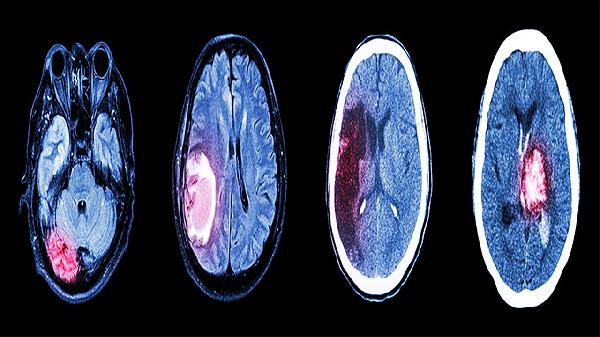

脑发育不良患者需建立长期管理计划,定期评估发育里程碑。家长应学习护理技巧,创造安全居家环境,避免跌倒等意外。保持规律作息,结合水疗、音乐疗法等多元刺激。社区康复与机构训练相结合,关注心理健康,必要时进行心理疏导。建议每3-6个月复查脑电图、头颅MRI等检查,动态调整治疗方案。